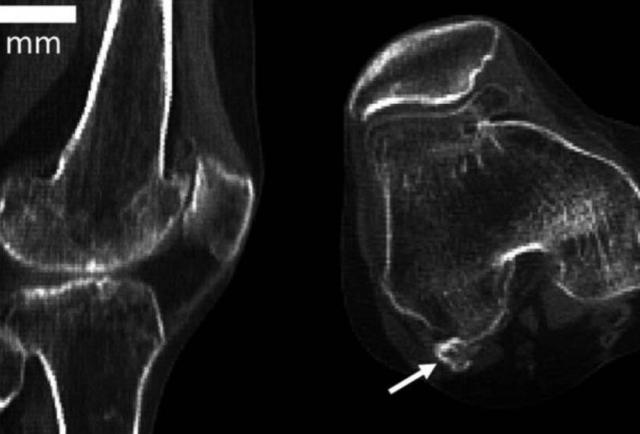

Las flechas indican la posición de fabela en las articulaciones actuales.

La fabela es un hueso sesamoide, es decir, un hueso redondeado, que crece en el tendón de un músculo (el mayor es la patela, o rótula). Por su tamaño y por lo poco común de su presencia, a veces en las radiografías se lo confunde con un fragmento óseo o un cuerpo extraño.